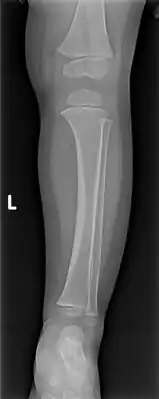

| A toddler's fracture | |

Toddler's fracture is a type of broken bone that involves the lower part of the shin bone (tibia).[1] Symptoms may include pain in the lower leg or a limp.[1] Some refuse to walk at all.[2]

The cause is often a twisting motion over a planted foot.[1] This may occur as the result tripping or other minor events.[1] It generally occurs in the distal thirds of the tibia, is undisplaced, and has a spiral pattern.[1] Diagnosis is often based on symptoms and examination, with initial X-rays appearing normal in about half of cases.[1]

The initial radiographical images may be inconspicuous (a faint oblique line) and often even completely normal.[7] After 1–2 weeks however, callus formation develops.

Accidental or innocent toddler fracture/frontal -

Accidental or innocent toddler fracture/lateral